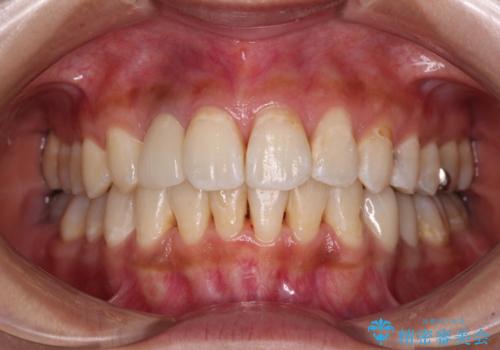

外科処置後の痛みを気にしていましたが、小規模の処置であったため、痛みを感じることはほとんどありませんでした。

気になっていた腫脹がなくなり、患者様には大変満足していただきました。